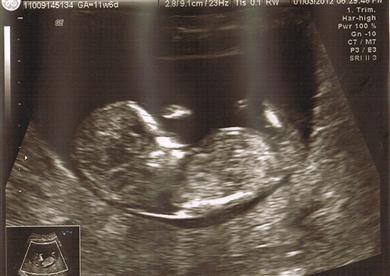

2nd pic is a no go.

1st pic, I wish I could see it bigger. Can you upload to your album and then post it again? From what I can see here, I think I see a "girl angle" nub, but I really need a bigger pic.

Hmm, not much bigger, but I think what I'm looking at is the nub, and it's definitely at a girl angle! Now, if that's not the nub, all bets are off, lol.